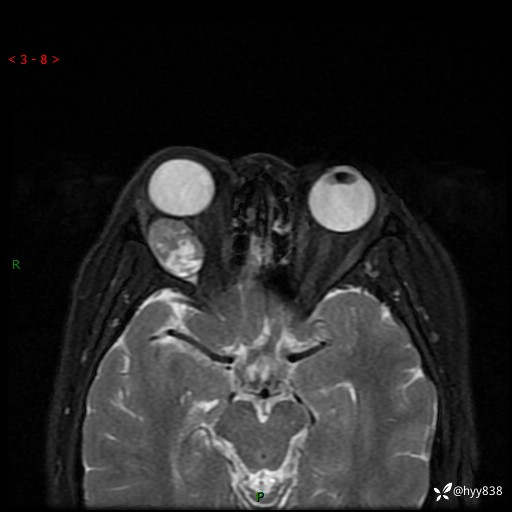

老年女性,右眼球突出1月。说说鉴别诊断,看谁第一个秒---(有结果)

主诉:发现右眼球突出1月余

简要病史:患者于1月前无明显诱因发现右眼球突出,偶感磨痛、眼胀,无视力下降,无头痛,恶心呕吐等不适。10天前就诊于当地县人民医院就诊,完善头颅ct检查,诊断为右侧眼眶肿物,建议患者上级医院进一步治疗,患者因个人原因拒绝。拟行手术,来我院就诊,门诊行相关检查后以“右眼眼眶肿物”收入院。 患病以来,患者精神饮食睡眠尚可,大小便如常、体重无明显改变。

辅助检查:MRI

临床诊断:眼眶肿物

眼眶MRI平扫+增强